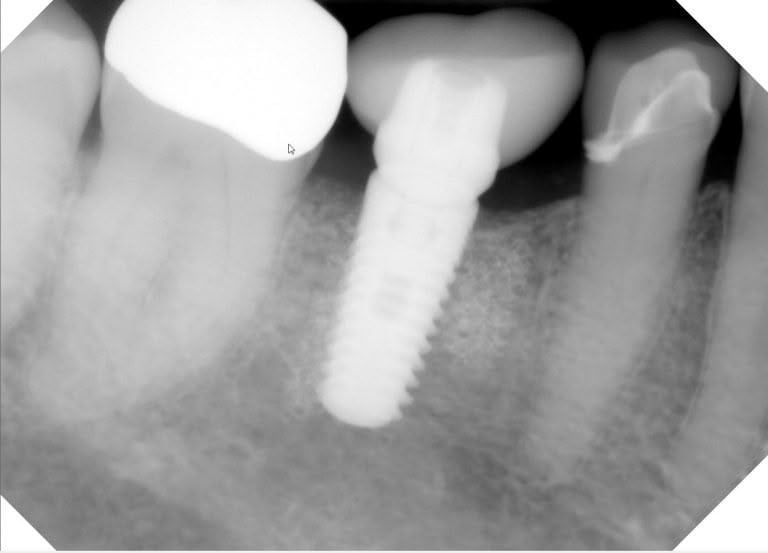

Periapical X-rays

Periapical x-rays capture the full length of 1 or more teeth, so that we can see the apex, or end, of the root. That’s where we look for signs of a tooth abscess, or infection. We also use them, as in this case, to make sure that dental implants are fully integrated in the bone.